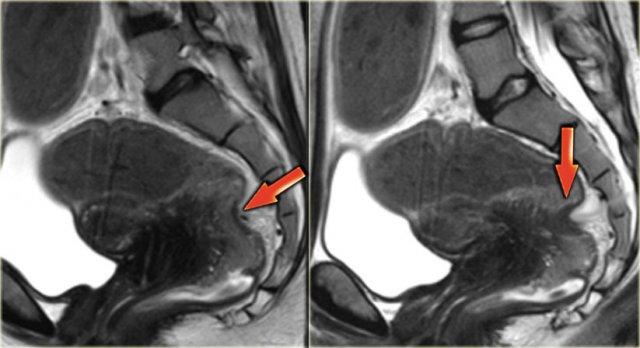

Hình ảnh T2W mặt phẳng đứng dọc này cho thấy lạc nội mạc tử cung xâm lấn sâu tại túi cùng sau với xâm lấn thành trực tràng.

Hình ảnh T2W của lạc nội mạc tử cung xâm lấn torus uterinus.

Hình ảnh T2W cho thấy lạc nội mạc tử cung xâm lấn sâu tại vòm âm đạo sau và torus uterinus.

Không có xâm lấn thành ruột.

Hình ảnh chuỗi xung T2W minh họa sự xâm lấn dây chằng tử cung-cùng bên trái.